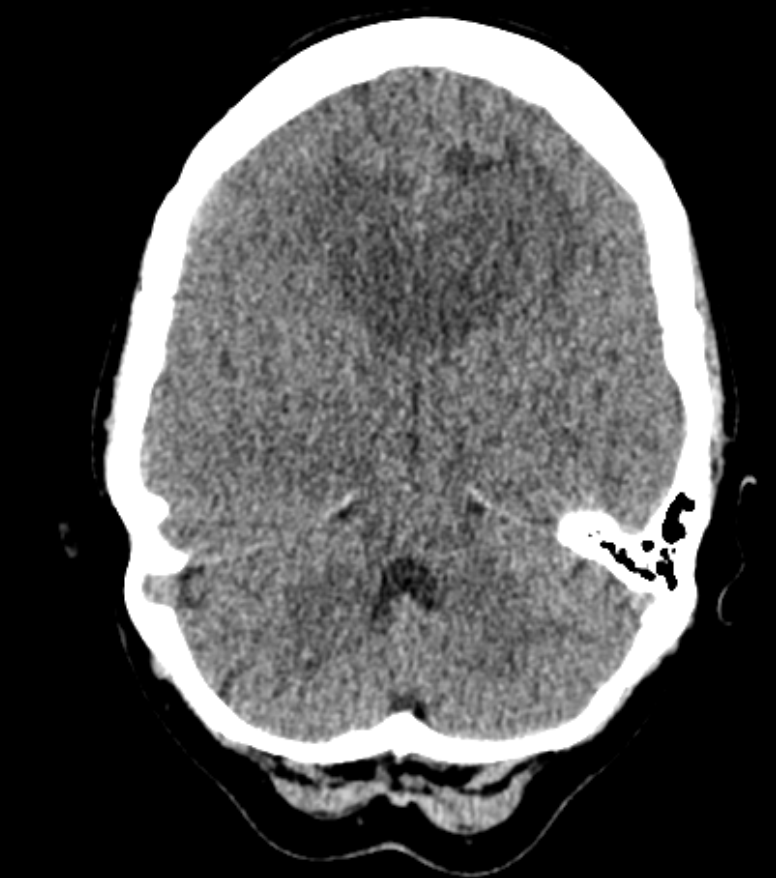

- CT: Enhancing deep lesions with surrounding oedema.

- MRI: Dense periventricular enhancing lesions, often homogeneously enhancing. May cross corpus callosum (โbutterflyโ). Dramatic but transient response to steroids ๐ฏ.

- Common sites: cerebrum, basal ganglia, thalamus, periventricular regions; can infiltrate optic nerves and eyes ๐๏ธ.

- Often presents as solitary but may be multifocal with angiocentric growth (around blood vessels).